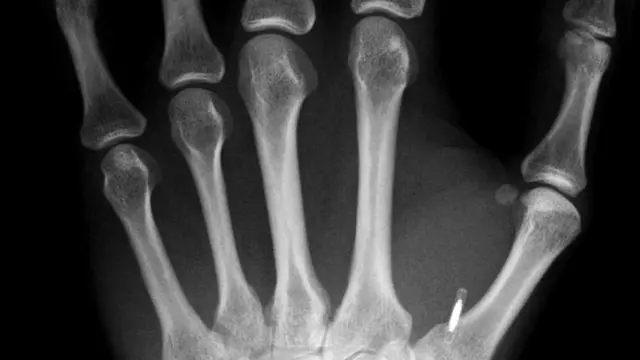

Для большинства будет совершенно незаметной эта горошинка размером с рисовое зернышко, вживленная в ткань ладони между указательным и большим пальцами.

Под кожей у Уильямса - вживленный микрочип, электронная схема, заключенная в крошечную стеклянную капсулу. Ее можно использовать примерно так же, как мы применяем бесконтактную платежную карту.

В данном случае Уильямс решил вживить себе чип устройства радиочастотной идентификации (RFID) - просто из любопытства. После процедуры вживления он превратился в ходячую бесконтактную смарткарту.